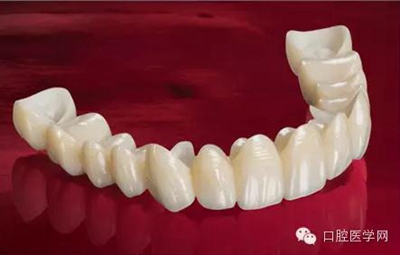

做完根管治療以后的牙齒,強(qiáng)度是有下降的,因?yàn)橹暗凝x壞,以及我們治療時(shí)為了讓器械能夠順利的進(jìn)入根管內(nèi)部,要磨除一些牙體組織。為了防止牙齒因?yàn)樽陨韽?qiáng)度下降而折斷,我們要給這個(gè)牙做一個(gè)全冠修復(fù),有時(shí)候在做冠之前還要在根管里放一個(gè)樁進(jìn)行加固。